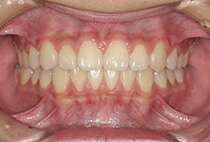

20代女性の患者さま。

八重歯の見た目が気になってご来院されましたが、実は顎の痛みや開口障害など、顎関節症の症状もありました。

そのため、かみ合わせと顎関節症の治療を同時に行ったにもかかわらず、2年間で治療が終了。

かみ合わせが整い咬筋の過緊張も改善しました。咬筋の肥大も治ってフェイスラインがすっきりしました。

最終的には美しい歯並びと、安定した痛みのないかみ合わせが実現しました。

八重歯が気になる

叢生、顎関節症、開口障害

20代女性

矯正治療2年

24回

唇側矯正

矯正:1,161,600円+毎月調整量:6,050円

しっかり前歯を下げるために、インプラントアンカーを使用してコントロールしました。

かみ合わせが整うと咬筋の過緊張が改善。

過緊張による筋肉肥大も改善しフェイスラインもすっきりしました。

治療前

治療後